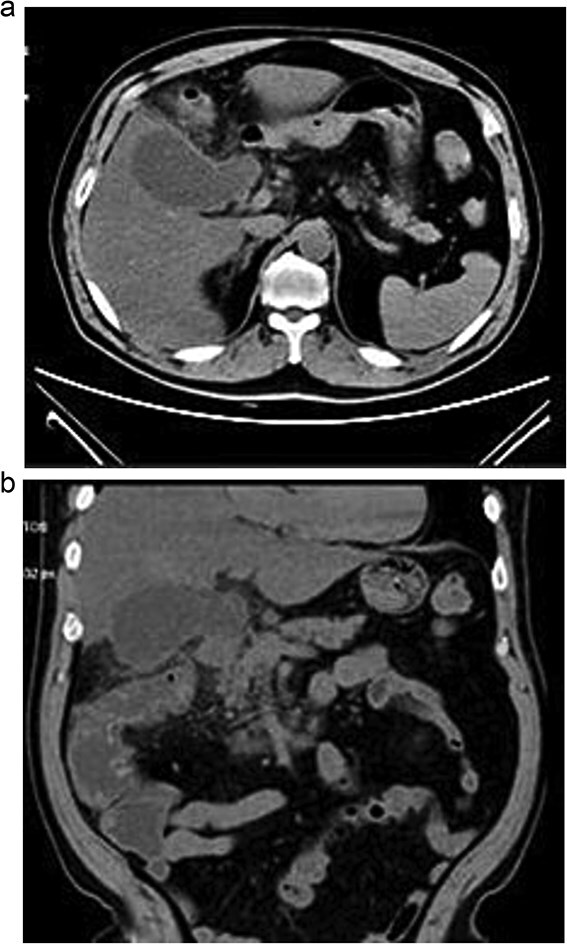

Gallbladder duplication is a rare congenital anomaly. Abnormal biliary anatomy is associated with an increased risk of complications, such as bile duct injury, during cholecystectomy. In this article, we present a clinical case of gallbladder duplication identified preoperatively by magnetic resonance cholangiopancreatography, which guided surgical planning. A 70-year-old man was admitted with acute cholecystitis, low-grade fever, jaundice, and dyspnea. Magnetic resonance cholangiopancreatography revealed a duplicated gallbladder (Type H). During surgery, the chronically inflamed upper gallbladder was completely resected. The larger lower gallbladder, with acute cholecystitis and a Mirizzi-like pattern, was partially resected due to severe inflammation and the inability to identify the cystic duct. The patient had an uneventful course. Gallbladder duplication is a rare congenital anomaly that may be associated with other congenital anomalies. Thorough preoperative imaging studies, meticulous surgical technique, and rigorous intraoperative monitoring are essential, as these abnormalities can lead to serious injuries.

Abstract Image